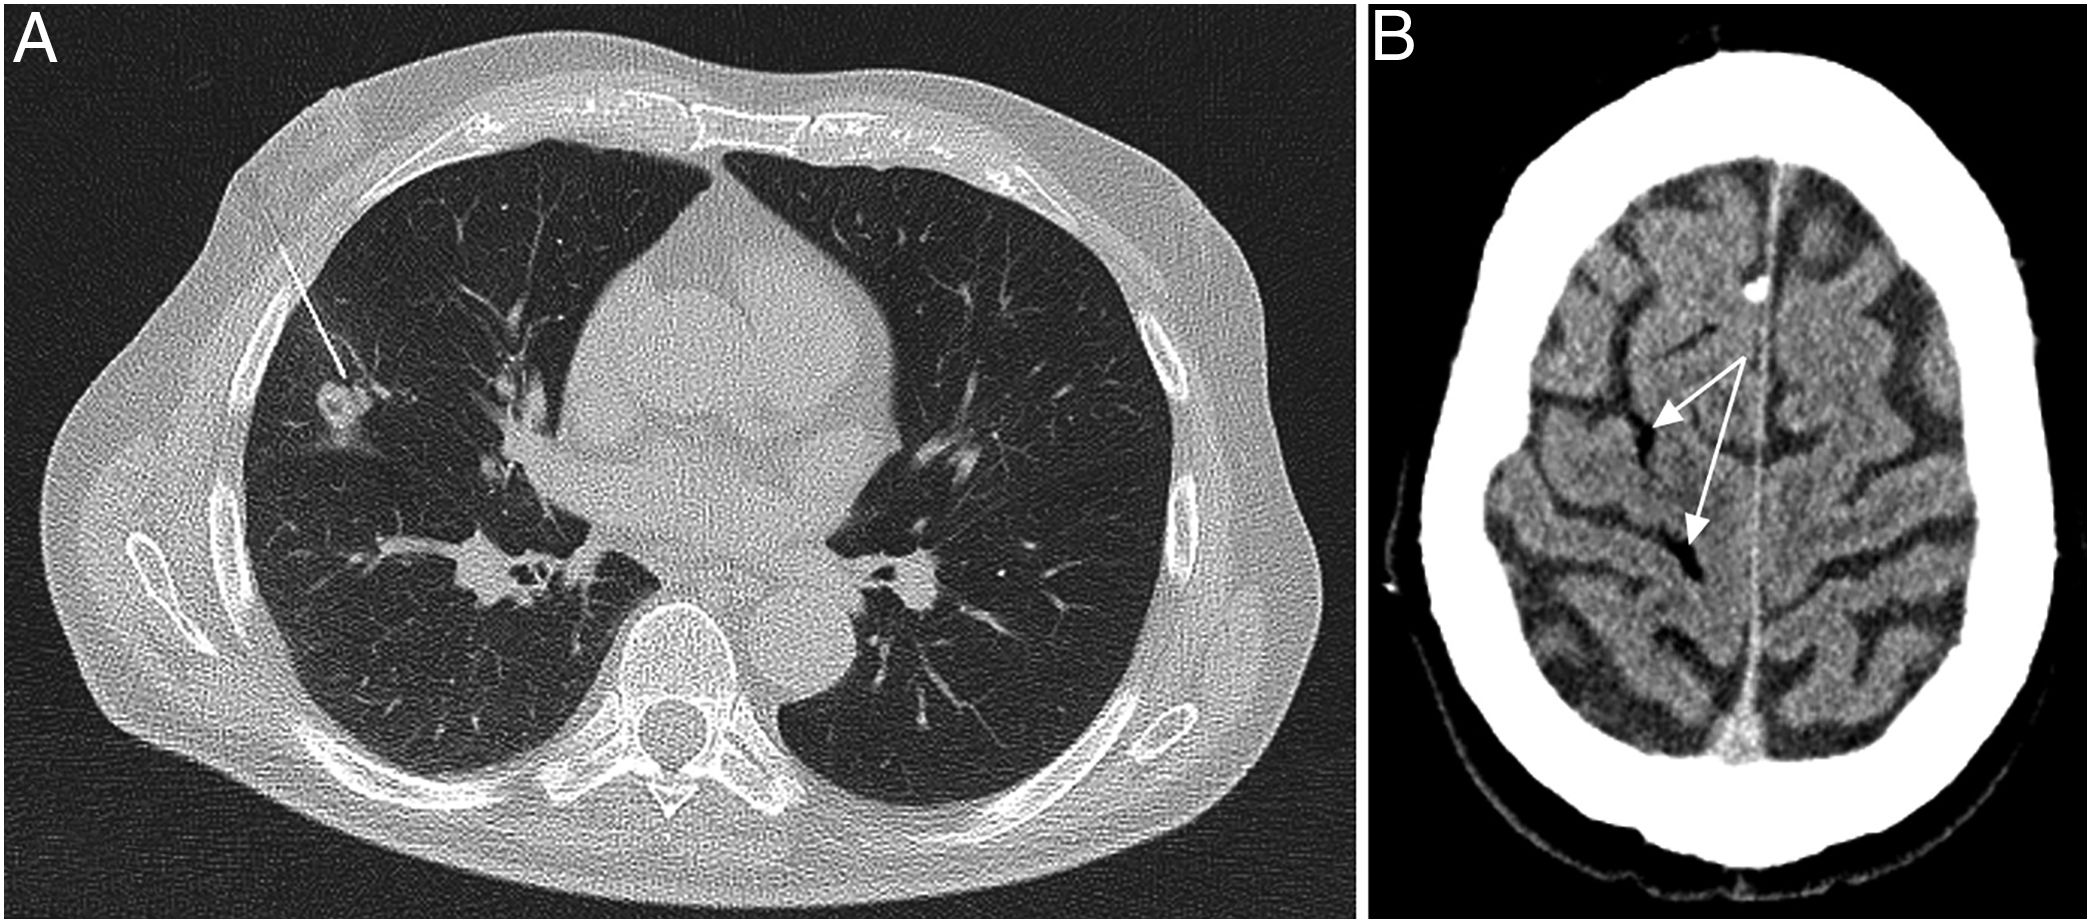

Radiología Embolia gaseosa arterial tras biopsia pulmonar percutánea

Embolia gaseosa arterial tras biopsia pulmonar percutánea

Arterial air embolism after percutaneous lung biopsy